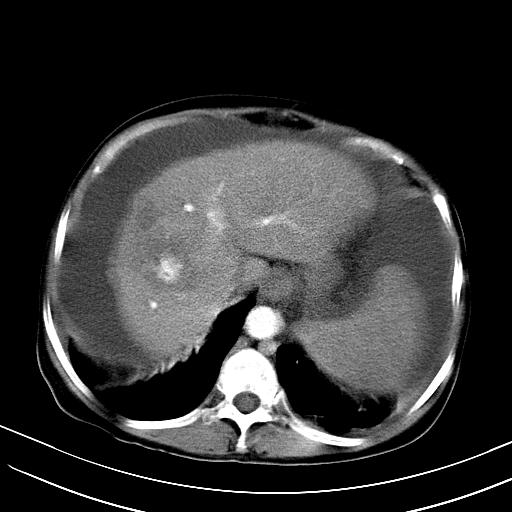

标题: CT23697:肝癌并肝动静脉漏? [打印本页]

标题: CT23697:肝癌并肝动静脉漏?

肝动静脉漏,动脉期肝动脉及门静脉内均可见造影剂……

1)肝右叶肝癌并肝动静脉漏。2)肝硬化,腹水。3)胆囊炎。

肝右叶肝癌并动静脉漏,肝硬化,腹水。

1)肝右叶肝癌并肝动静脉漏 门v右支瘤栓伴海绵样变。2)肝硬化,脾大 腹水。3)胆囊炎。门v高压.

右叶肝癌并肝动静脉漏(动脉期肝动脉及门静脉内均可见造影剂),肝硬化,腹水。(胆囊壁水肿)

1)肝右叶肝癌,考虑并发肝动静脉漏。扫描时间好像慢了。2)肝硬化,门脉高压、脾大、腹水。